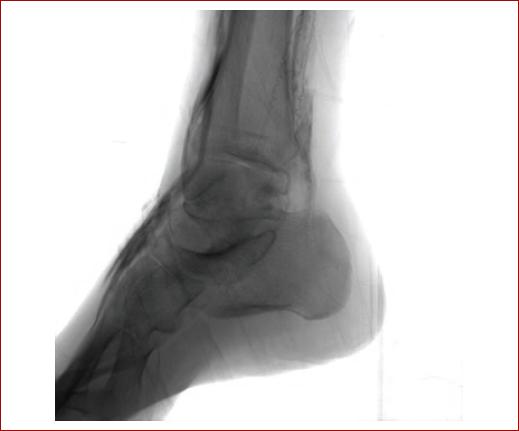

Al día siguiente y en el contexto de la infección sistémica, se realiza amputación transmetatarsiana en guillotina, sin complicaciones, verificando una adecuada perfusión del lecho cruento (Fig. 5). Se maneja en el postoperatorio con rivaroxabán 10 mg cada 24 horas por vía oral, cilostazol 100 mg vía oral y ácido acetilsalicílico 100 mg cada 24 horas por vía oral. Se egresa al paciente sin complicaciones.

Figura 5 Amputación transmetatarsiana en guillotina, sin sangrado pulsátil, pero con adecuada viabilidad del tejido y microperfusión.

Seis meses después de la revascularización, el paciente continúa con evolución satisfactoria de la herida, sin recidiva del dolor, con adecuada granulación y sin reincidencia del dolor isquémico (Fig. 6). A la realización de Doppler de onda continua en miembros pélvicos se obtiene un índice tobillo -brazo de 0.6 derecho y de 0.6 izquierdo.